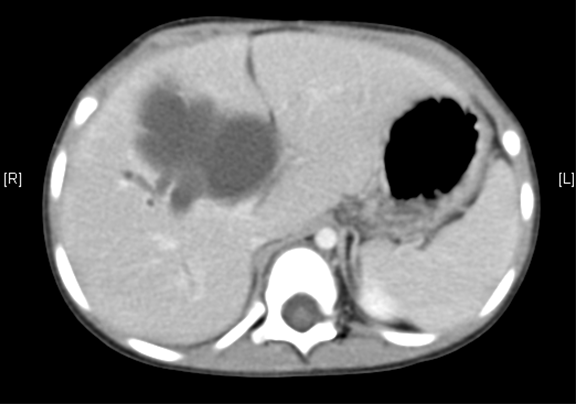

腹部CT 增强:1. 肝内外胆管扩张,考虑胆总管囊肿并胆系扩张可能性大2. 胆囊结石。

将0.625mm双源薄层CT资料的静脉期和动脉期Dicom格式文件导入海信CAS系统。

通过调节窗宽窗位调整CT序号,对肝实质,胆囊,下腔静脉,肿瘤,肝动脉、门静脉及肝静脉等进行三维重建;系统自动计算肝脏体积。

术前CT检查:

动脉期

静脉期

平衡期